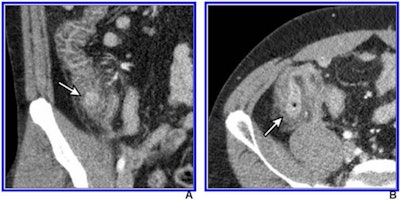

The results could help clinicians better distinguish right colonic diverticulitis from appendicitis, noted a team led by Dr. Hae Young Kim, PhD, of Seoul National University Bundang Hospital in South Korea.

"By mitigating concern of missed diagnosis of right colonic diverticulitis, our results further support the use of low-dose CT for suspected appendicitis," the group wrote in a paper published on 8 April in the American Journal of Roentgenology.